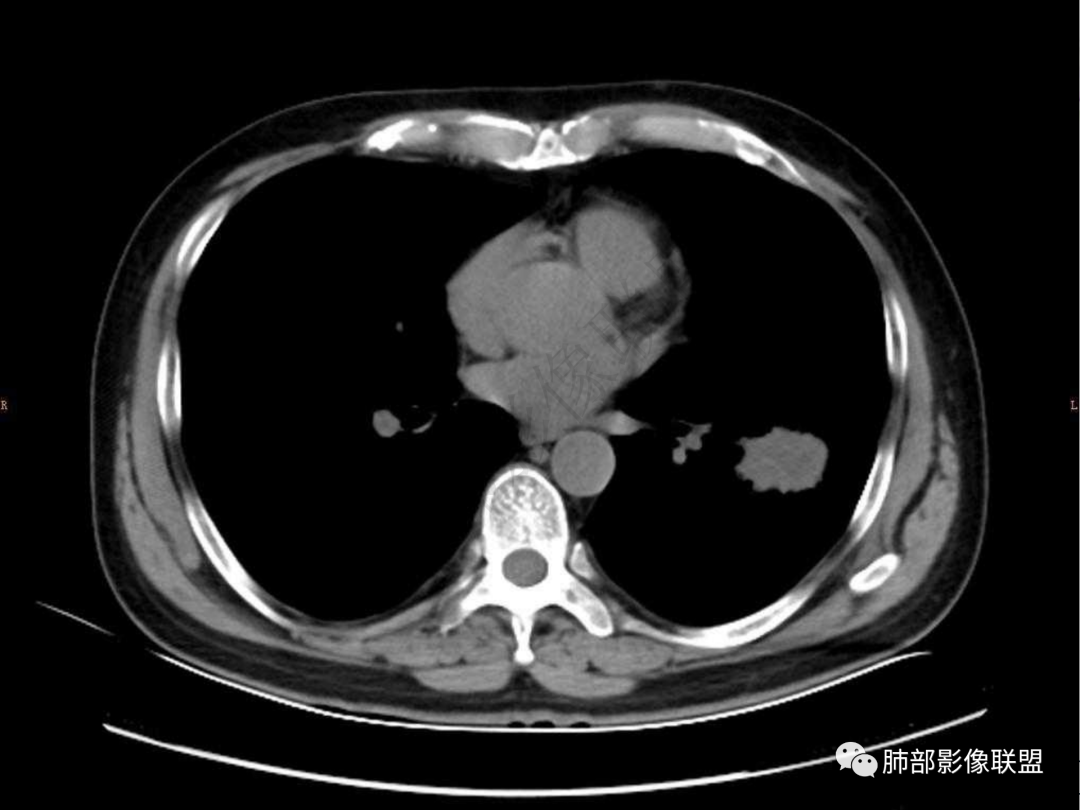

4.实性部分不均匀环形强化并显示一小范围低密度坏死区或空洞。较之肺窗,整体纵隔窗范围较小,提示病灶并不十分密实。抑或为不同时段图像。

肺脓肿:边界模糊不清,或者块影为类圆形,无明显分叶,边缘平直为主,刀切征——炎性特点三、病灶周围特点:肺脓肿:病灶非远端有片状GGO——炎性特点四、近端支气管阻塞:肺脓肿:常有引流支气管伴管壁增厚或者支气管沿洞壁走行。五:坏死壁:肺脓肿:大多壁厚,少数壁薄,没有壁结节,内壁清楚光整——炎性特点

六:增强扫描:

肺脓肿:环形强化,强化较显著。如出现明显囊壁样强化甚至边缘“憩室”样突出,高度支持肺脓肿。